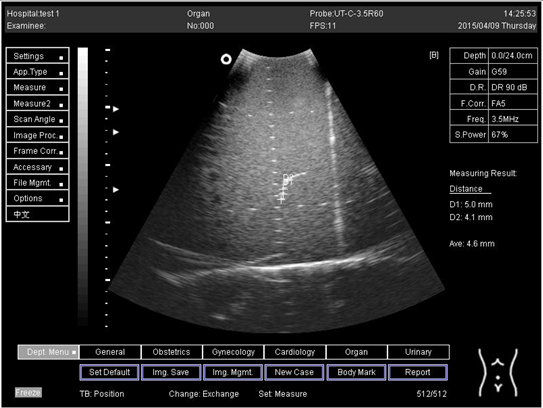

18.0Axial resolution

Biomimetics 07 00130 i019

D1 = 5.0